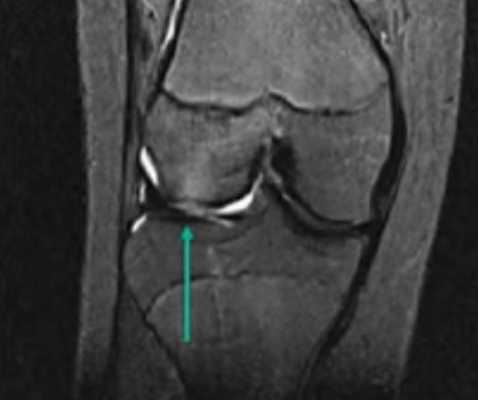

МРТ коленного сустава показывает наличие кисты Бейкера в подколенной ямке (обозначена стрелкой)

Возможно ее обратное развитие вплоть до полного исчезновения, но при условии своевременной диагностики и лечения. При длительном её существовании содержимое кисты затвердевает, формируется спаечный процесс. Возможен ее разрыв, приводящий к появлению острых болей, отеку в подколенной ямке и области голени. В таком случае особое значение приобретает МРТ, которая дает возможность провести дифдиагностику с другими патологиями.